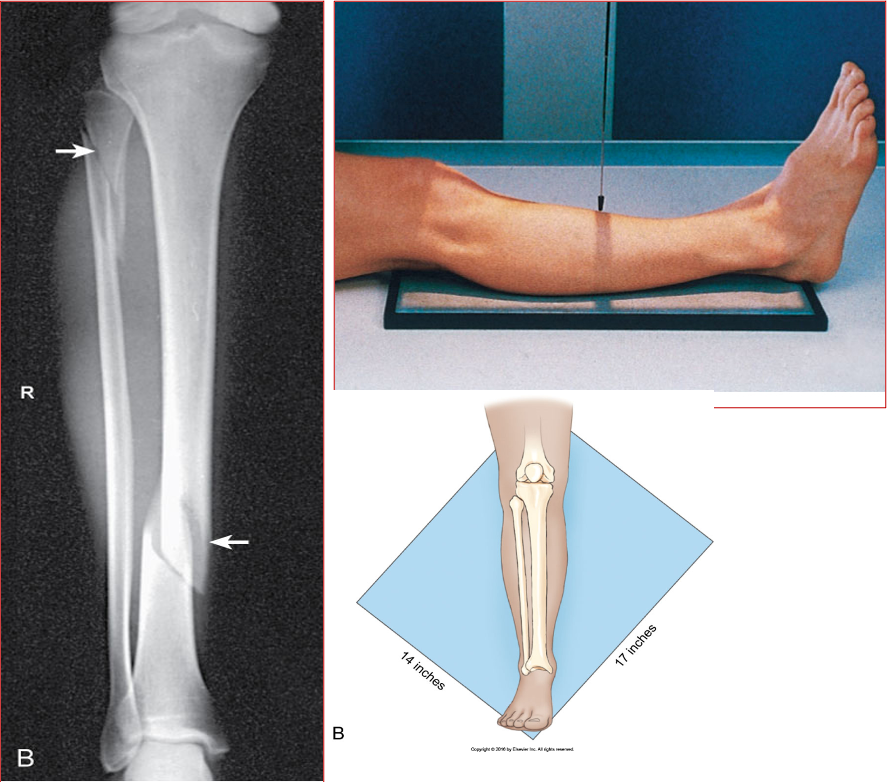

AP Tib/Fib

• IR 14x17 portrait (or diagonally), 48” SID

• Pt supine with leg extended fully. Align pelvis, knee & leg to true AP position (no rotation). Dorsiflex foot 90º. Ensure ankle and knee joints are 1-2” from either end of IR to prevent divergent rays from projecting anatomy off the image. If leg will not fit on IR, do 2 projections, use smaller IR to include other joint.

• CR perpendicular to midpoint of lower leg. Collimate to include as much of the knee and ankle joint as possible.